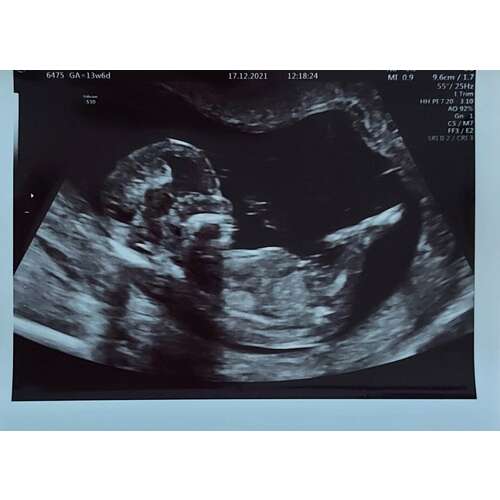

Iemand enig idee wat het wordt? Is een 12 weken echo.

Ik denk een meisje